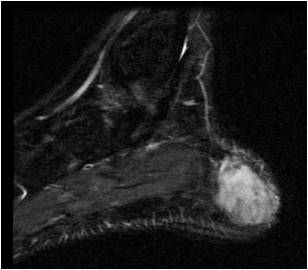

Pleomorphic liposarcoma is a malignant, or cancerous, soft-tissue tumor that most commonly occurs intramuscularly or subcutaneously. It is the least common subtype of liposarcomas, however treated similarly to other liposarcomas, including surgical resection or removal of the tumor.